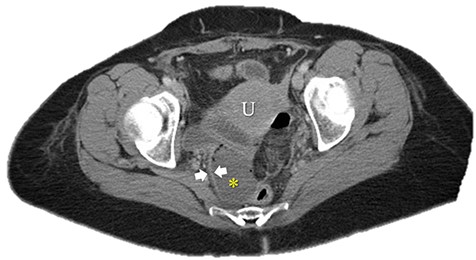

Immediate postoperative course was uneventful until postoperative day (POD)-5 when she experienced multiple watery stools, diffuse abdominal pain, fever (102.6F) and leukocytosis (23000/UL). Clostridium difficile infection was ruled out with a negative stool toxin assay. Her abdominal exam remained nonspecific until POD-6 when she had bilious emesis. A computed tomography (CT) scan revealed perforated diverticulitis with pelvic abscess and multiple colonic diverticulitis with an associated small bowel obstruction (SBO) (Images 1–4). No prior history of diverticulitis was reported.

Axial image of pelvic collection. U: uterus; *: pelvic abscess cavity; White arrows: rim-enhancing pelvic abscess cavity.